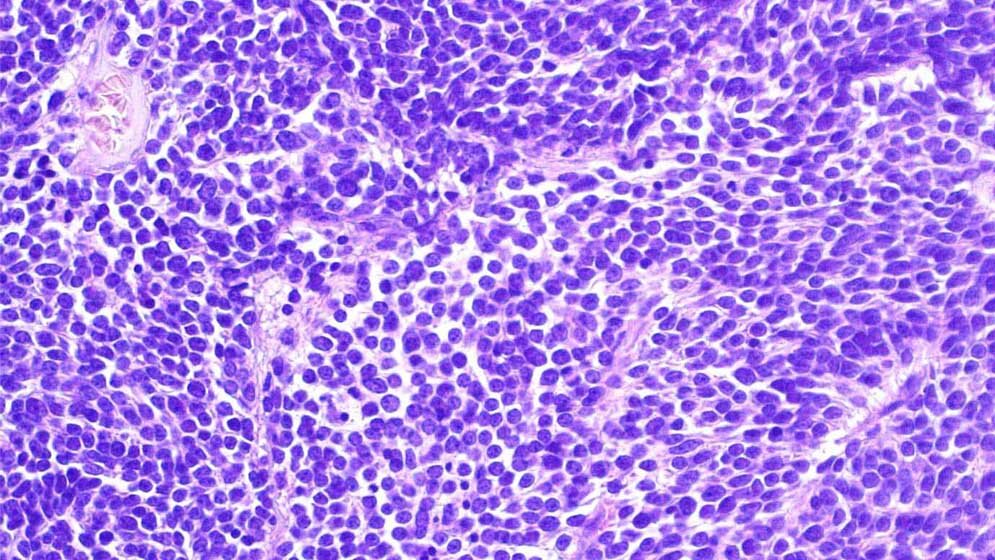

Oft unterscheiden sich mikroskopisch ähnliche Hirntumoren auf molekularer Ebene stark voneinander – Unterschiede, die bei der Wahl des Behandlungsverfahrens berücksichtigt werden müssen. Kinder, die an embryonalen Hirntumoren erkrankt sind, müssen meist besonders intensive, beschwerliche Therapien durchlaufen. Sie haben – abhängig von ihrer Tumoruntergruppe – oft dennoch nur geringe Heilungschancen. Das trifft auch für die sogenannten „supratentoriellen primitiven neuroektodermalen Tumoren“ (sPNETs) zu: Diese Krebsformen gehen aus unreifen Zellen des Zentralnervensystems (ZNS) hervor und wachsen daher besonders schnell und aggressiv.

Im speziellen Fall der vorliegenden Studie stellte sich durch die Methylierungsuntersuchung heraus, dass nur wenige Patienten tatsächlich ein sPNET hatten und ein erheblicher Teil stattdessen biologisch eindeutig ein sogenanntes kleinzelliges Glioblastom. Auch Ependymome und andere seltenere Tumorarten verbargen sich im Sammelsurium von mikroskopisch als sPNET diagnostizierten Tumoren. Wenn man diese „Falschklassifizierten“ herausrechnet, ist bei sPNET die Prognose deutlich besser als seit Jahrzehnten angenommen und die Patienten sprechen mit größerer Wahrscheinlichkeit auf die Chemotherapie an.